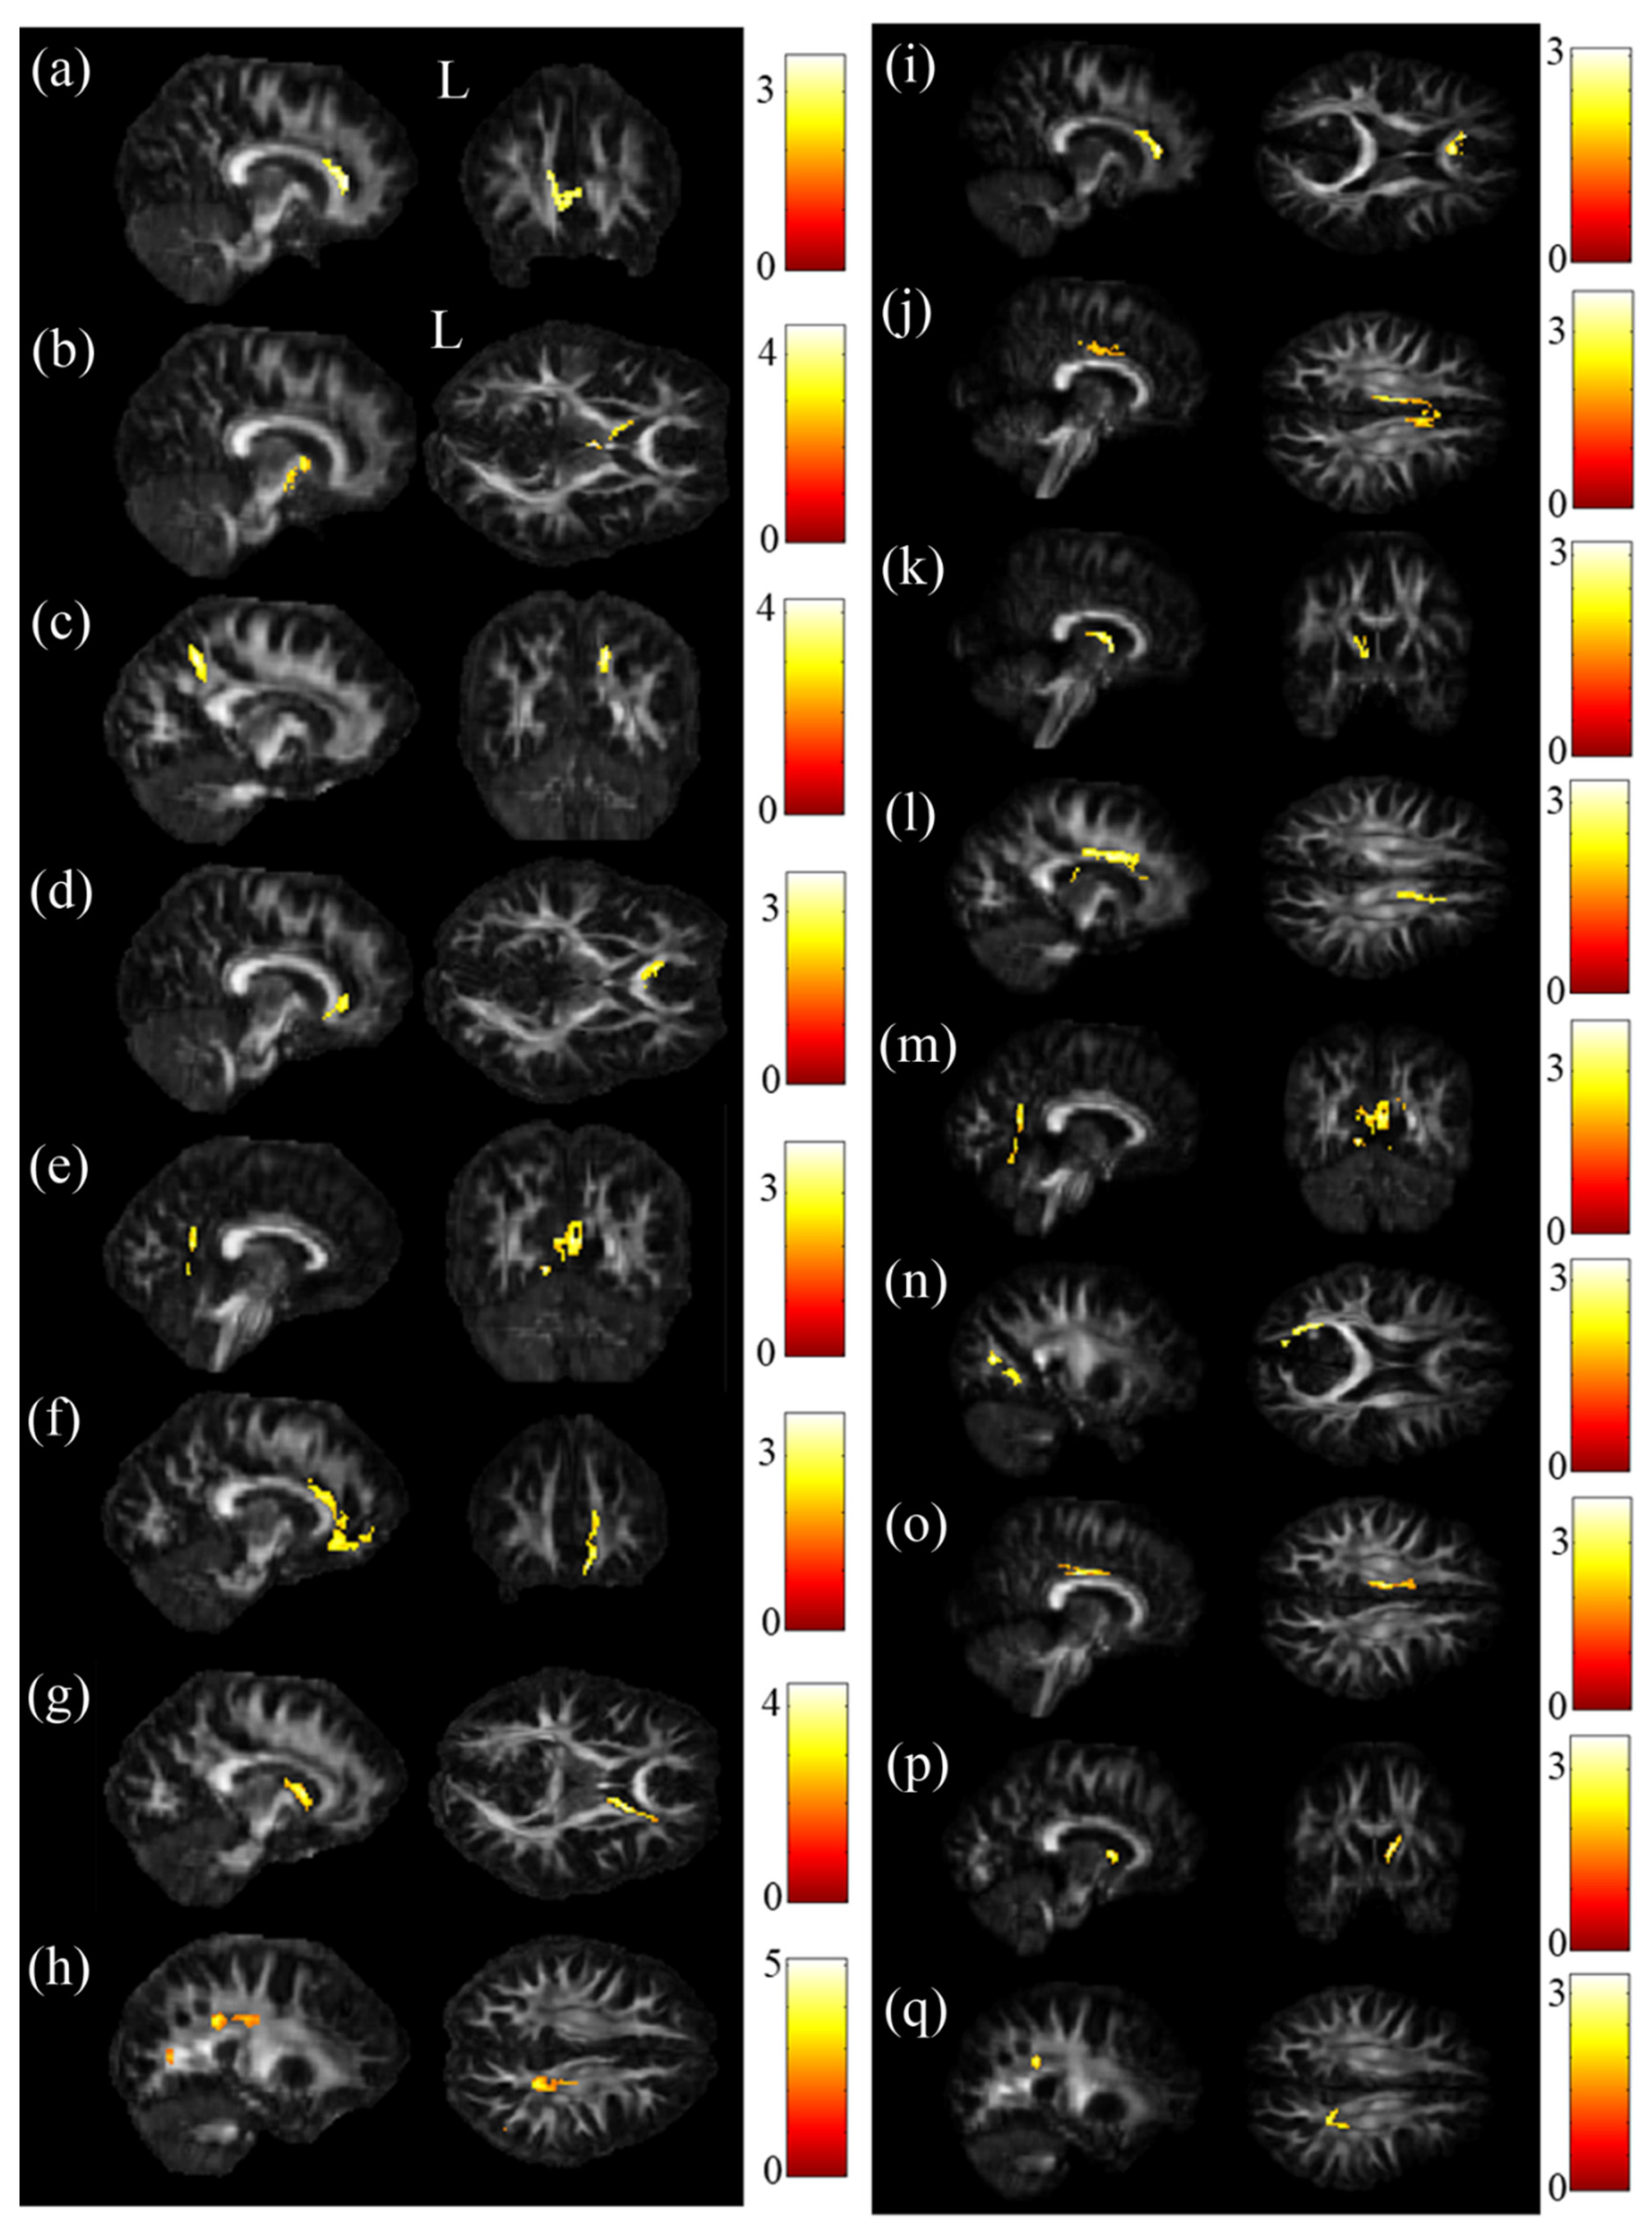

The ANCOVA results demonstrated that the GFA value showed significant differences in the cingulate gyrus and precuneus (Figure 1a,b), and the NQA value showed significant differences in the cingulate gyrus and caudate (Figure 1c) (p < 0.05). Then, post hoc two-sample t-tests were performed to assess GFA and NQA values among these brain regions. In two-sample t-tests, both GFA and NQA values of the corpus callosum, cingulate gyrus and caudate were significantly lower in the SA group than in the HC group (Figure 2a,b,i–k). Additionally, the precuneus had a lower GFA value in the SA group than in the HC group (Figure 2c). In the comparison between the SA group and the D group, both the corpus callosum and precuneus had notably lower GFA and NQA values in the SA group than in the D group (Figure 2d,e,l,m). Additionally, the cuneus had a lower value of NQA in the SA group than in the D group (Figure 2n). In the comparison between the D group and HC group, both GFA and NQA values of the cingulate gyrus, caudate and precuneus were remarkably lower in the D group than in the HC group (Figure 2f,g,h,o–q). Furthermore, the cuneus had a lower GFA value in the D group than in the HC group (Figure 2h).

Figure 2.

Post hoc t-test results. Compared with the HC group, significantly lower GFA values in the (a) corpus callosum, cingulate gyrus, (b) caudate and (c) precuneus occurred in the SA group. Compared with the D group, the SA group had significantly lower GFA values in the (d) corpus callosum and (e) precuneus. Compared with the HC group, the D group had significantly lower GFA values in the (f) cingulate gyrus, (g) caudate and (h) precuneus. Compared with the HC group, significantly lower NQA values in the corpus (i) callosum, (j) cingulate gyrus and (k) caudate occurred in the SA group. Compared with the D group, significantly lower NQA values in the (l) corpus callosum, (m) precuneus and (n) cuneus occurred in the SA group. Compared with the HC group, the D group had significantly lower NQA values in the (o) cingulate gyrus, (p) caudate and (q) precuneus (p < 0.05, cluster size > 100, color bar: t scores).